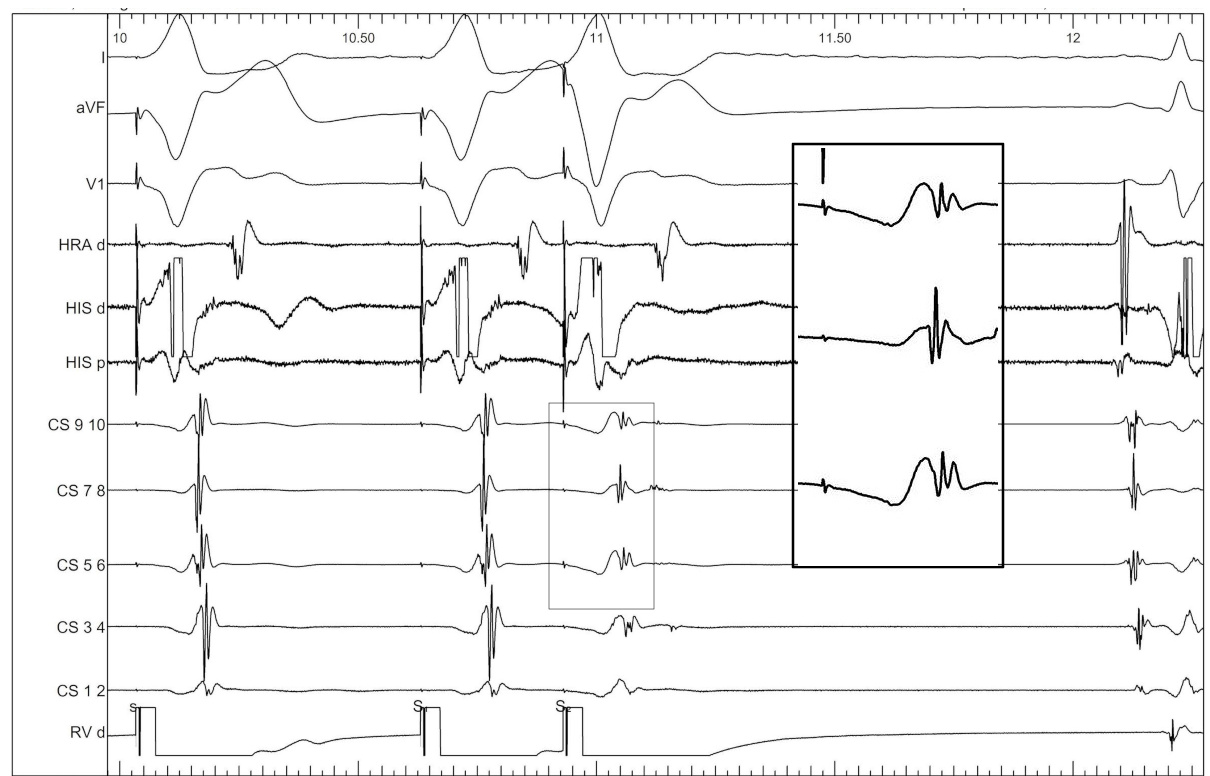

Entrain when ablating free wall AP during tachycardia

entrain_ablate.jpg